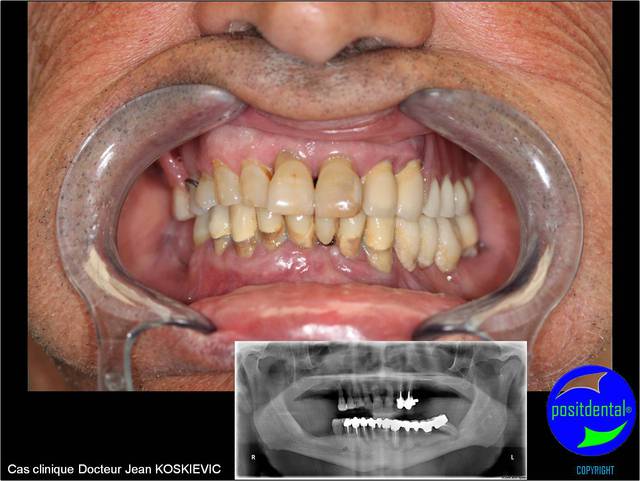

03/05/2011 à 17h47

photo pré opératoire

Wax up 3d positdental 13 qz0t5p - Eugenol

rendu 3D maxillaire sup, pano et photo